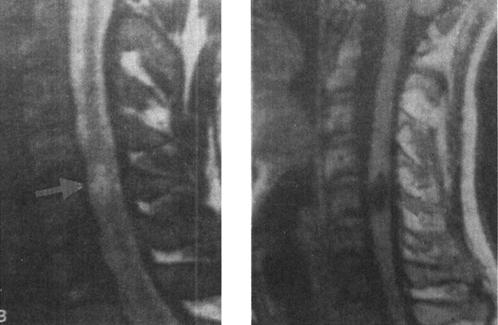

图7-12b MRI矢状面T1WI可见颈髓在C5水平明显受压,椎体前缘和椎管内可见中等偏高信号,局部颈髓可见斑点状高信号;12WI被压迫的脊髓亦见高信号出血灶,脊椎前方前纵韧带下血肿,呈高信号

(5)脊髓横断:脊髓横断表现为脊髓和硬膜囊连续性中断,在矢状面显示清楚。完全性横断可伴有脊髓的回缩,两断端出现较宽的间隙。MRI检查T2WI较T1WI敏感,可清楚显示横断的脊髓,尤其是在T2WI,脑脊液呈高信号,而脊髓呈中等信号,两断端间充满高信号的脑脊液(图7-18)。不完全性脊髓横断,在T2W呈高信号,脊髓连续性尚存。

图7-18 T11椎体骨折脱位伴脊髓横断性损伤:T1W(a)和T2Wb矢状面示,T10以上明显向前脱位,椎管和脊髓在T11水平中断和成角,脊椎前、中、后柱骨折脱位,并有脊柱周围血肿